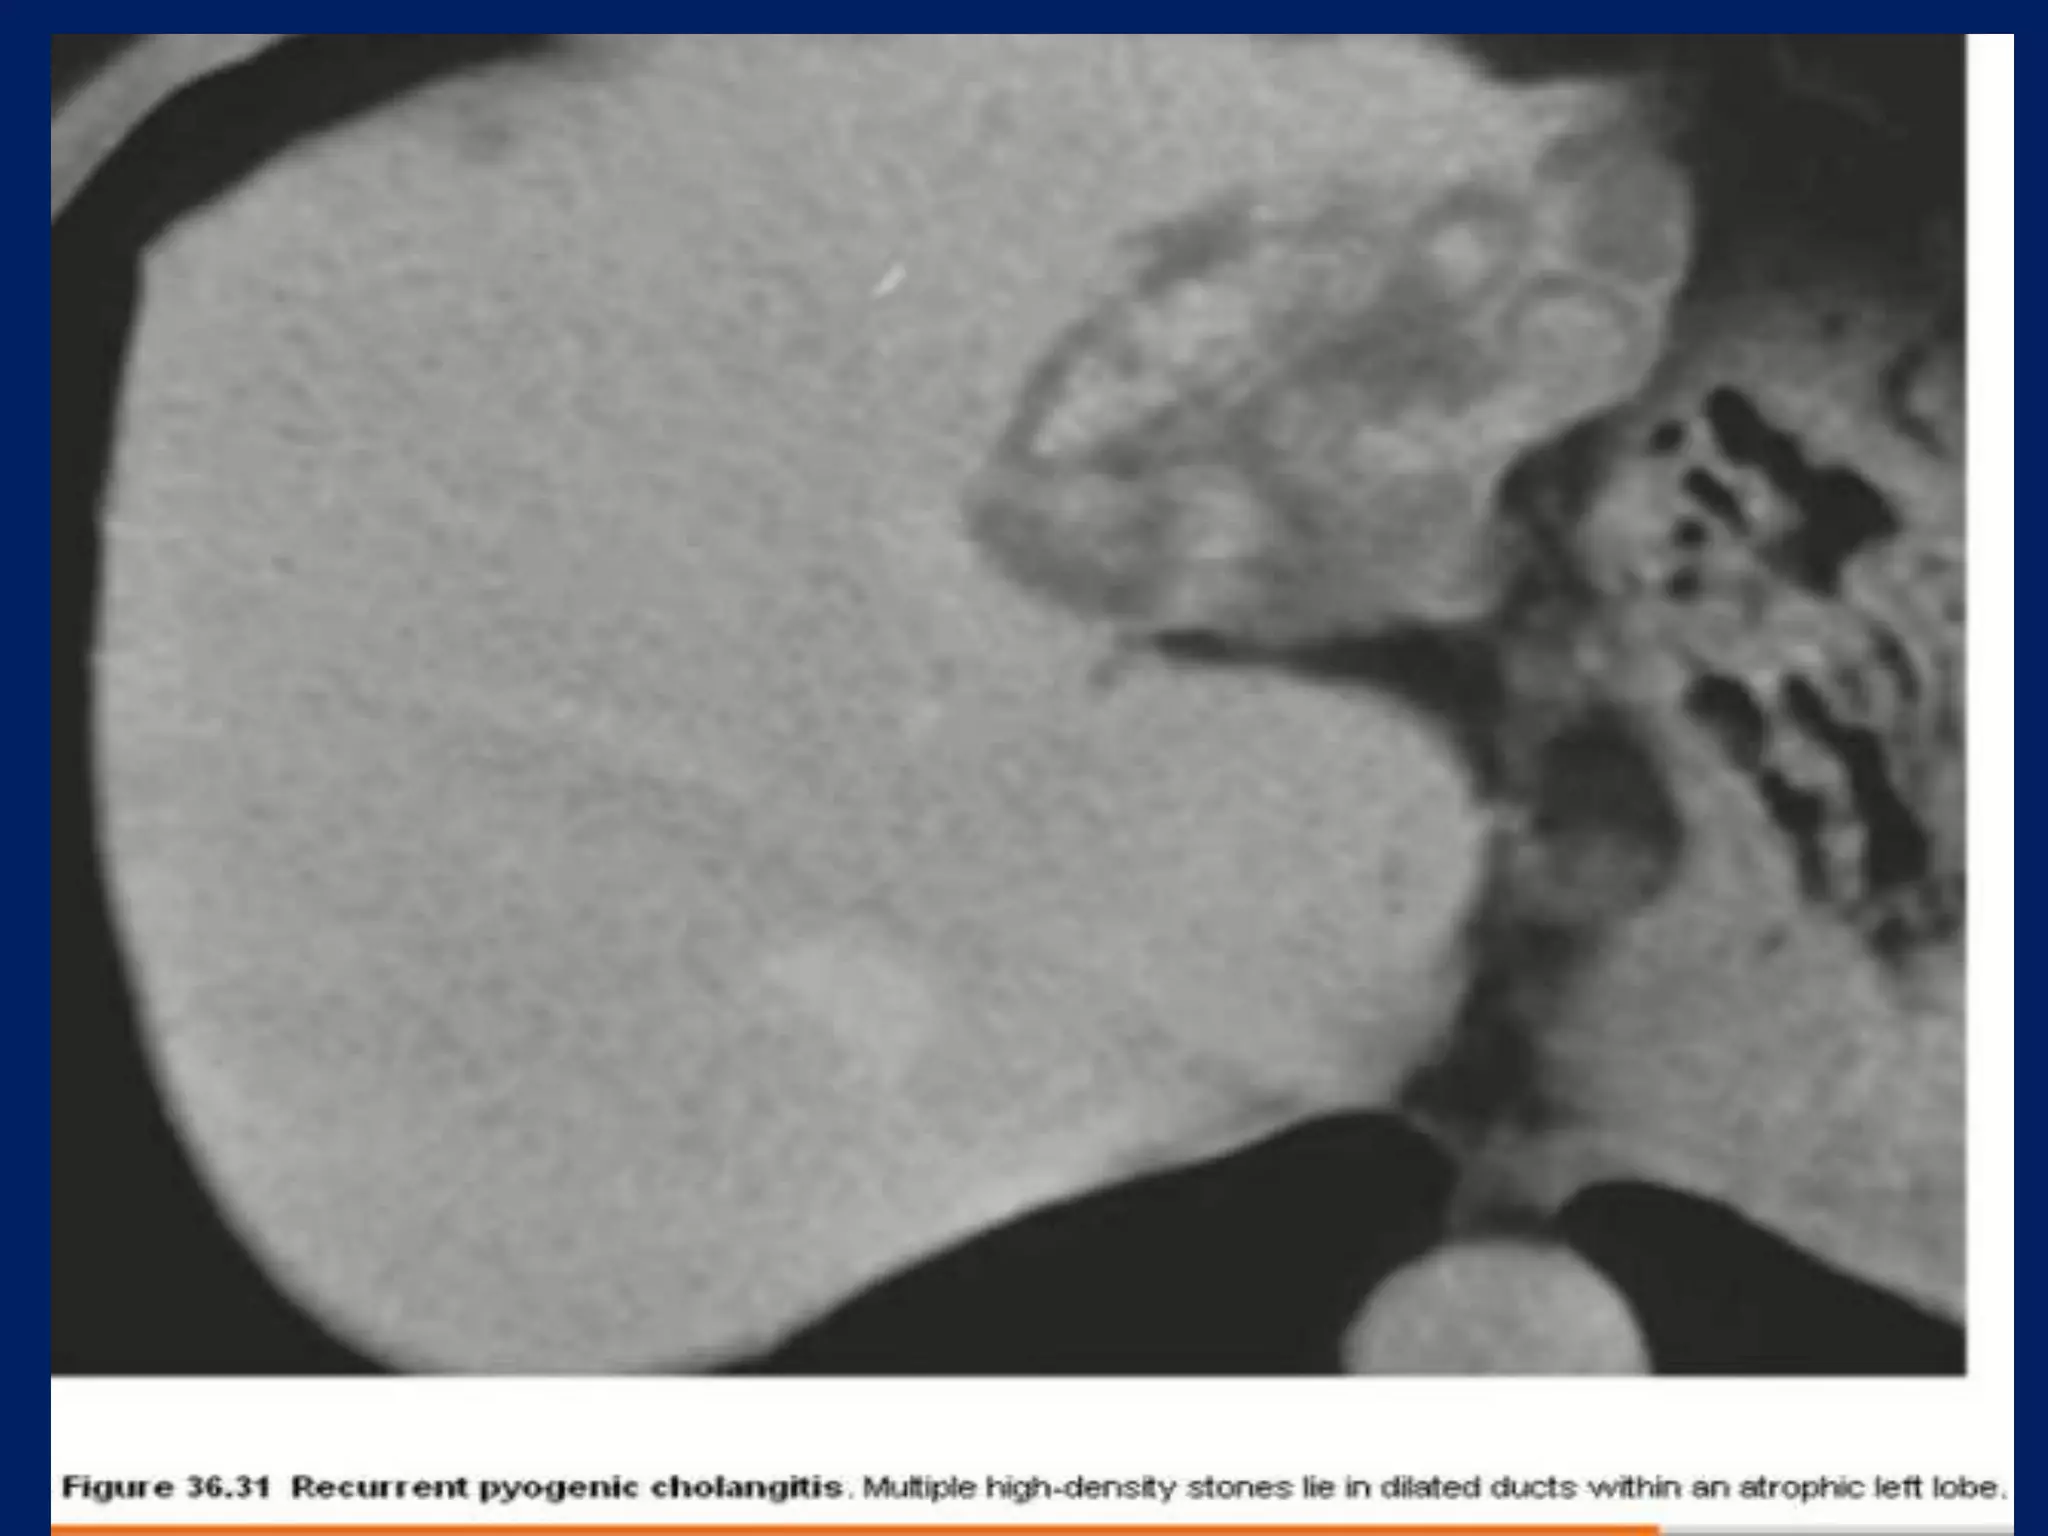

This document discusses imaging techniques for evaluating the biliary system. It covers common bile duct stones and Mirizzi's syndrome, which involves compression of the common bile duct by gallstones. It also mentions biliary cystadenoma, a type of cyst forming in the bile ducts or gallbladder.